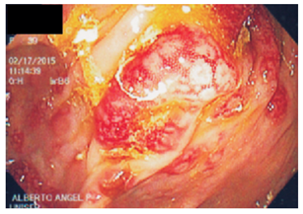

La colonoscopia reporta un pólipo grande en el ciego, de aproximadamente 5 cm de diámetro, que engloba el orificio apendicular, pétreo, del que se toman biopsias. Además, muestra otros múltiples pólipos sésiles de 3 a 15 mm de diámetro, hipervascularizados, con elasticidad conservada, que dan aspecto granuloso a la mucosa a lo largo de todo el colon, incluido el recto. Se toman biopsias. Se hace impresión diagnostica del pólipo gigante en el ciego, para descartar cáncer y poliposis múltiple del colon (Figuras 1, 2, 3 y 4).